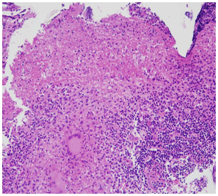

Patient was admitted and started on empirical intravenous antibiotics. Mantoux test was negative. An attempt of lumbar puncture was unsuccessful. High Resolution Computed Tomography of temporal bone was suggestive of an ill defines iso-dense heterogeneously enhancing lytic expansile lesion involving left jugular bulb causing erosion of squamous part of temporal bone, clivus, mastoid part of temporal bone with thrombosis of left sigmoid sinus and internal jugular vein (Figure 1). Post contrast Magnetic Resonance Imaging of brain revealed an ill-defined moderately heterogeneous enhancing lesion of left jugular bulb causing erosion of squamous part of occipital bone and extending into pre and para vertebral space up to level of C1 vertebra and causing destruction of mastoid part of temporal bone with thrombosis of left sigmoid sinus and internal jugular vein (Figure 2). Cranial Magnetic Resonance Imaging venography showed thrombosis in left sigmoid sinus and internal jugular vein (Figure 3). Blood investigations ruled out the presence of hypercoagulable state in our patient.

Figure 1 High Resolution Computed Tomography of temporal bone: Erosion of squamous part of temporal bone, clivus and mastoid part of temporal bone on left side.